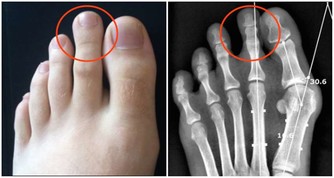

超聲科醫師檢查發現其右側陰囊空虛,右側腹股溝內可見大小約2*2*1cm的類睾丸迴聲,診斷考慮:隱睾症。

超聲科劉友員主任醫師解釋,“蛋蛋”不在陰囊裡就是俗稱的“隱睾症”。

隱睾,是指睾丸在正常發育過程中未下降或下降不全至陰囊,陰囊內沒有睾丸或只有一側有睾丸。

正常睾丸大小約4*3*2cm,位於陰囊內,

陰囊是最適合睾丸生長發育的場所,陰囊內溫度比體溫低1° C-2°C,有利於睾丸產生精子。

而隱睾患者睾丸未進入陰囊,長期留在腹腔和腹股溝管內,這些部分局部溫度高,

可導致睾丸生精細胞損害,影響精子的產生和生存,易導致不育。

目前超聲檢查是最簡便,快捷無創的檢查方法,它不僅可檢查隱睾所在的位置,還可測量隱睾大小。